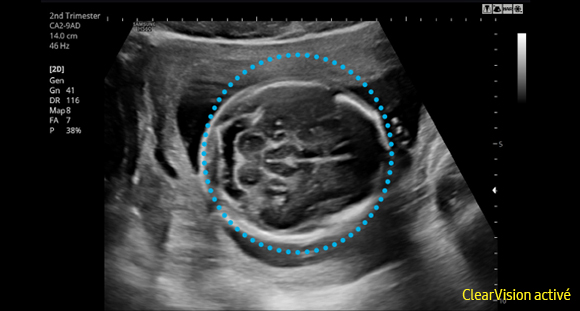

Le filtre de réduction de bruit ClearVision améliore les contours d'une structure anatomique et augmente le rapport signal sur bruit. Il permet de délivrer des images 2D plus nettes et augmente la différenciation tissulaire.